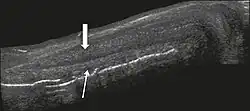

The corpora cavernosa are homogeneous and relatively hypoechoic cylindrical structures lined with tunica albuginea, a thin membrane that has a thickness of approximately 2 mm when the penis is flaccid and 0.25 mm when it is erect. The corpus spongiosum, a ventral, medial body that is more echoic than the corpora cavernosa, is also covered by the tunica albuginea and contains the urethra. As can be seen in Figures 1 and 2, it is more dilated and prominent in its proximal segment, known as the bulb, and in its distal segment, constituting the glans. Buck's fascia is superficial to the tunica albuginea and covers all of the structures described.[1]

Venous drainage is performed by the deep and superficial dorsal veins of the penis. The dorsal arteries of the penis are located adjacent to the deep dorsal vein and a cavernous artery is located in the center of each corpus cavernosum. On color Doppler, the cavernous arteries present single phase flow. In the flaccid penis (Figure 3), the normal cavernous arteries show a systolic peak between 11 and 20 cm/s. At the beginning of erection, the systolic and diastolic flows undergo progressive increases. When vein occlusion begins, the diastolic flow decreases progressively, and once stiffness is established, it becomes negative.[1]